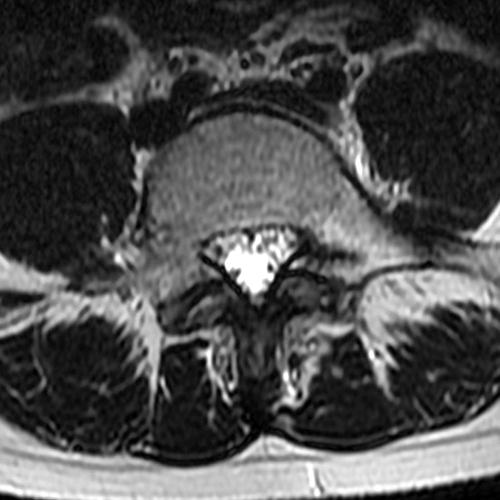

Case 1: 14-year-old female with back pain after a car accident. Axial T2-weighted (1A) and sagittal STIR (1B) images are provided. What are the findings? What is your diagnosis?

Case 1: T2-weighted axial (3A) and sagittal STIR (3B) sequences show marked cortical T2/STIR hyperintensity in the left pedicle of L5 surrounding a hypointense line (arrows) which begins at the inferior/medial margin of the pedicle and nearly completely traverses the pedicle.

Case 1: Acute left-sided pediculolysis